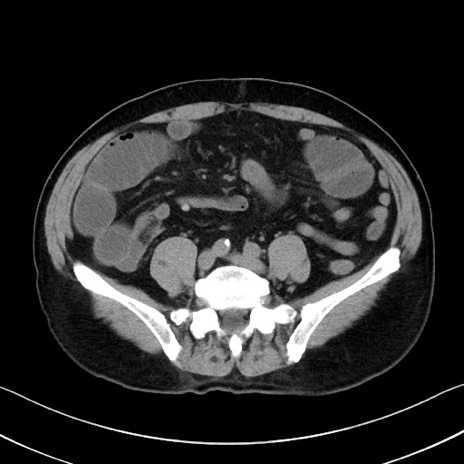

冠状断像

【症例】70歳代 男性

【主訴】腹部膨満、嘔吐

【現病歴】昨日より腹部膨満感出現。本日増悪し、仙痛出現。嘔吐あり、受診。

【既往歴】糖尿病、胆摘後

【身体所見】BP 149/80mmHg、HR 74/min、BT 35.9℃、腹部:膨満、軟、圧痛なし。腸雑音減弱あり。上腹部正中切開瘢痕あり。

【データ】WBC 13500、CRP 1.72